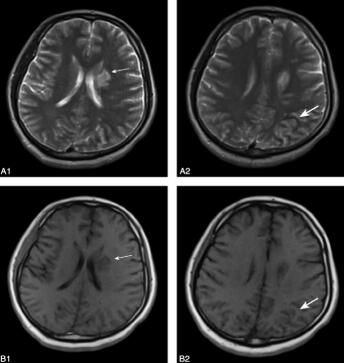

第二次MRI(6月15日):左顶叶病灶范围较前有所扩大,左侧豆状核、侧脑室旁及半卵圆中心新发病灶,左侧额、颞、顶、枕叶脑回肿胀(图2)。

图2 2011年6月15日复查头颅MRI示:左顶叶病灶范围较前有所变大,左侧豆状核、侧脑室旁及半卵圆中心可见斑点状或片状异常信号;A1.T2WI左侧尾状核处可见大片新发高信号影(细箭头);A2.T2WI图像上可见左顶叶病灶较前明显增大,呈高信号(粗箭头);B1.T1WI左侧尾状核处可见大片新发低信号影(细箭头);B2.T1WI图像上可见左顶叶病灶较前明显增大,呈略低信号(粗箭头)